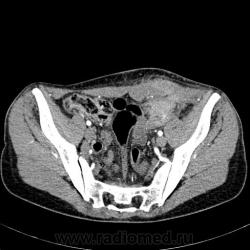

КТ живота. Женщина 40 лет, напрвавлена на КТ таза с подозрением на остеому левой подвздошной кости. В течении месяца заметила припухлость в левой подвздошной области, затем небольшая болезненность. Проведена Р-графия костей таза, снимков не видел, но по заключению рентгенолога единственно, что у него вызвало сомненте  - это подозрение на сакроилеит, рекомендовал Р-графию крестцовоподвздошных в косых проекциях. Выполнено УЗИ брюшной полости и гинекологическое УЗИ- без особых замечаний.  Дайком можно закачать с https://public.me.com/dr.mario1 живот аноним.

Мда... Не повезло.  Видимо, проекция этого образования вызвала у рентгенолога подозрение на сакроилеит. Что это такое? Миосаркома какая-нибудь? Есть инвазия кишки?

Бог его знает, что это... Может, автор подскажет? но уж очень выраженное накопление контраста, держится прилично и видно зоны некроза, отек клетчатки, жидкость в тазу...

Складывается впечатление о раке сигмовидной кишки с инвазией в брюшную стенку. Редко, конечно, но такое бывает.

Качество проведенного исследования отличное, предположу тоже о наличие "cr сигмы" с инфильтрацией прямой мышцы живота и канцероматозом малого таза+лимфоаденопатия.

Я к тому, что это может быть малигнизация эндометриоза, визуально образование отлично накапливает конрастное вещество, а может эндометриойдная карцинома яичника-фантазия вслухСмешно. А в матке спираль?

А что с клиникой? В малом тазу жидкость с ограничением, какие то отдельные кисты, плотность только смущает до 24HU, а ещё имеется солидный компонент накапливающий контраст, стенки кальнированые, в данном случае все наводит на мысль о злокачественном новообразовании, хоть и дела давние, только что первично. Ждем автора.

Согласен, тут что-то есть, но не понятно тогда почему на УЗИ пишут, что без особенностей... Как раз область яичника. Это может оказаться образованием яичника (Ex: эндометриоидной кистой, карциномой - много неправильных кист), они могут и по брюшине так же распространяться с вовлечением кишок. При эндометриоидной кисте долна быть хотя какая-то связь с циклом, но автор об этом не пишет, это один из важных диагностических признаков. Еще бы натив посмотреть на плотность..., оценить, есть ли геморрагичеакий компонент, но смущает брюшная стенка... Кстати, нельзя забывать, что примерно в четверти процентах случаев зла яичников - мтс и чаще всего жкт...

Пациентка амбулаторная, а потому верификации пока ждать не приходится, если смогу проследить - сообщу гистологию. Моё мнение, что имеется опухолевое поражение передней брюшной стенки исходящее из прямой мышцы живота с распространением в брюшную полость, инфильтрацией большого сальника и передней стенки сигмовидной кишки на ограниченном участке. Сигма прослежена на всём протяжении, просвет визуализирован. Сама пациентка на активные распросы по поводу проблем с кишечником говорит, что всё ОК. Плотность образования в нативном исследовании 42 ед.Х., в артериальную 80, в портальную ещё подкопило до 89 ед.Х. Подкожножировая клетчатка в месте прилежания опухоли тоже инфильтрирована. В Дугласе жидкость есть и кистозное образование левого яичника, тоже был удивлён заключением гинекологического УЗИ. По поводу шумов, режем по 2 мм, реконструирую по 3 мм, всё гладенько.